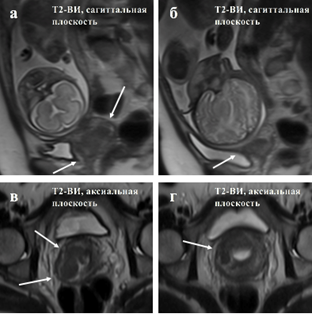

КТ ретроперитонеального фиброза: Изображения и диагностика